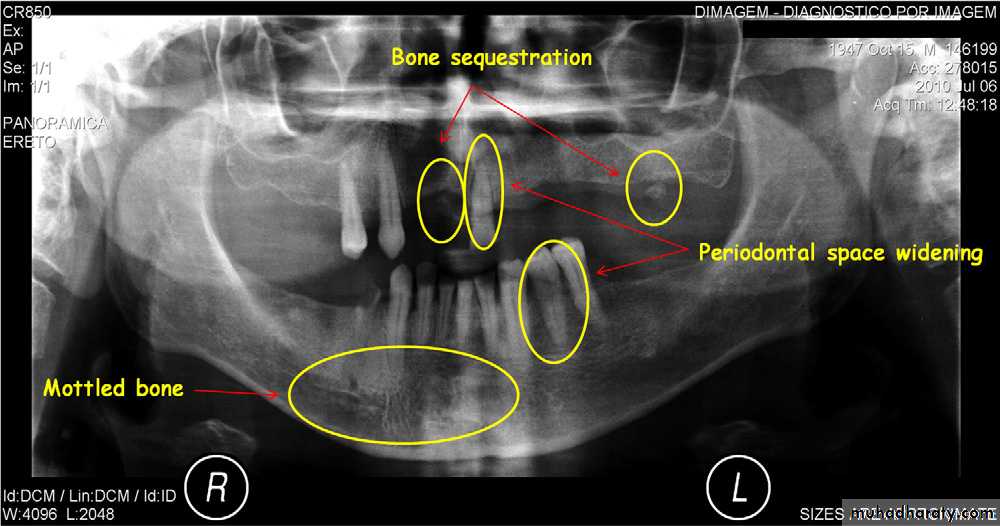

( A and B ) of the same patient taken 1 year apart demonstrate a developing sclerotic bone pattern with a sequestra (arrow) related to bisphosphonate therapy.

• Presence of sequestra . • Increase in bone sclerosis. • Widening of PDL space • Thicknening of lamina dura.

Location: *posterior mandible.Periphery: Better defined than the acute phase. In acute exacerbation periphery is radiolucent.

Internal structure: Lesion is more radiopaque and may be equivalent to cortical bone. Small regions of radiolucency may be scattered .

Effects on surrounding structures: New periosteal bone in series of radioqaue lines (onion skin) parallel to the cortical bone surface.